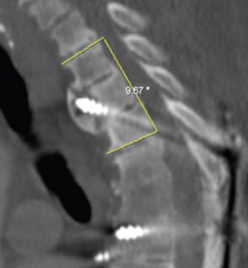

Ø 术后PI-LL不匹配,PI-LL大于10°

图21 术后PI-LL不匹配,大于10°